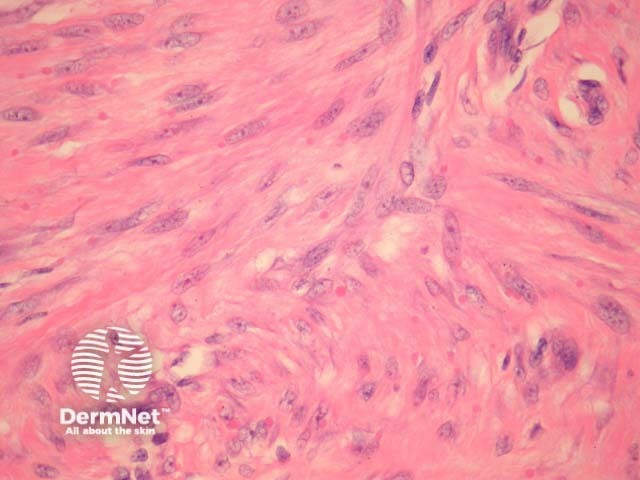

In infantile digital fibromatosis, sections show an intradermal unencapsulated tumour composed of spindle-shaped cells arranged in whorls or interdigitating sheets (figure 1). These myofibroblasts contain 3–10 μm inclusion bodies, which are round or ovoid and granular (figures 2-4, arrows are used to highlight some of the inclusion bodies in figure 2).

The inclusion bodies stain pink with H&E (figures 2-4). The bodies are positive with immunohistochemical stains for actin and vimentin.